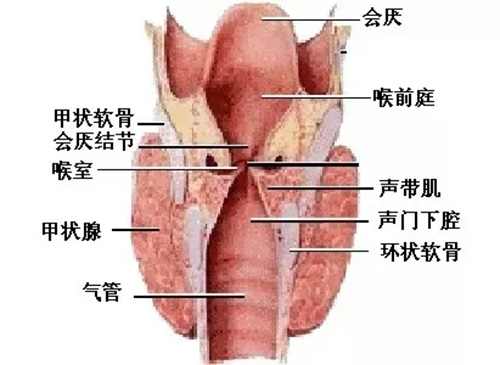

喉癌预防 咽喉癌的早期症状 喉癌是怎么引起的 喉癌的症状 喉癌基础